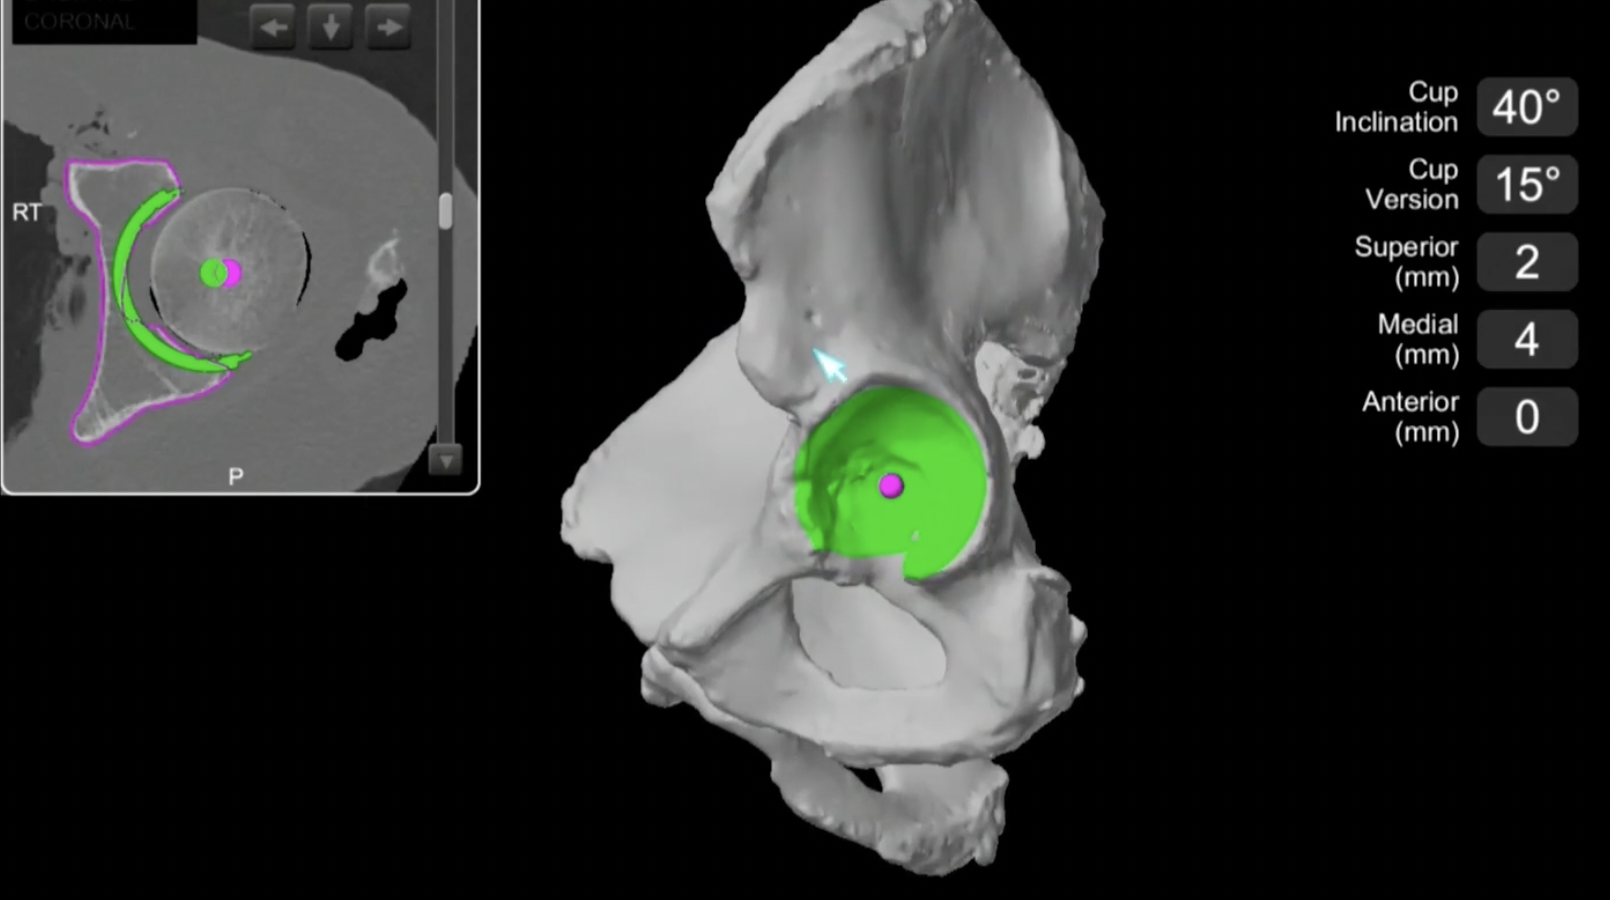

CT templating

Advantage

- extremely precise especially with femoral anteversion / cup inclination and anteversion

- evaluates bone stock

- identify osteophytes

Accuracy

Hassani et al J Arthroplasty 2024

- preoperative CT templating in 50 uncemented THA

- 100% accurate femoral stem stize

- 94% accurate acetabular size